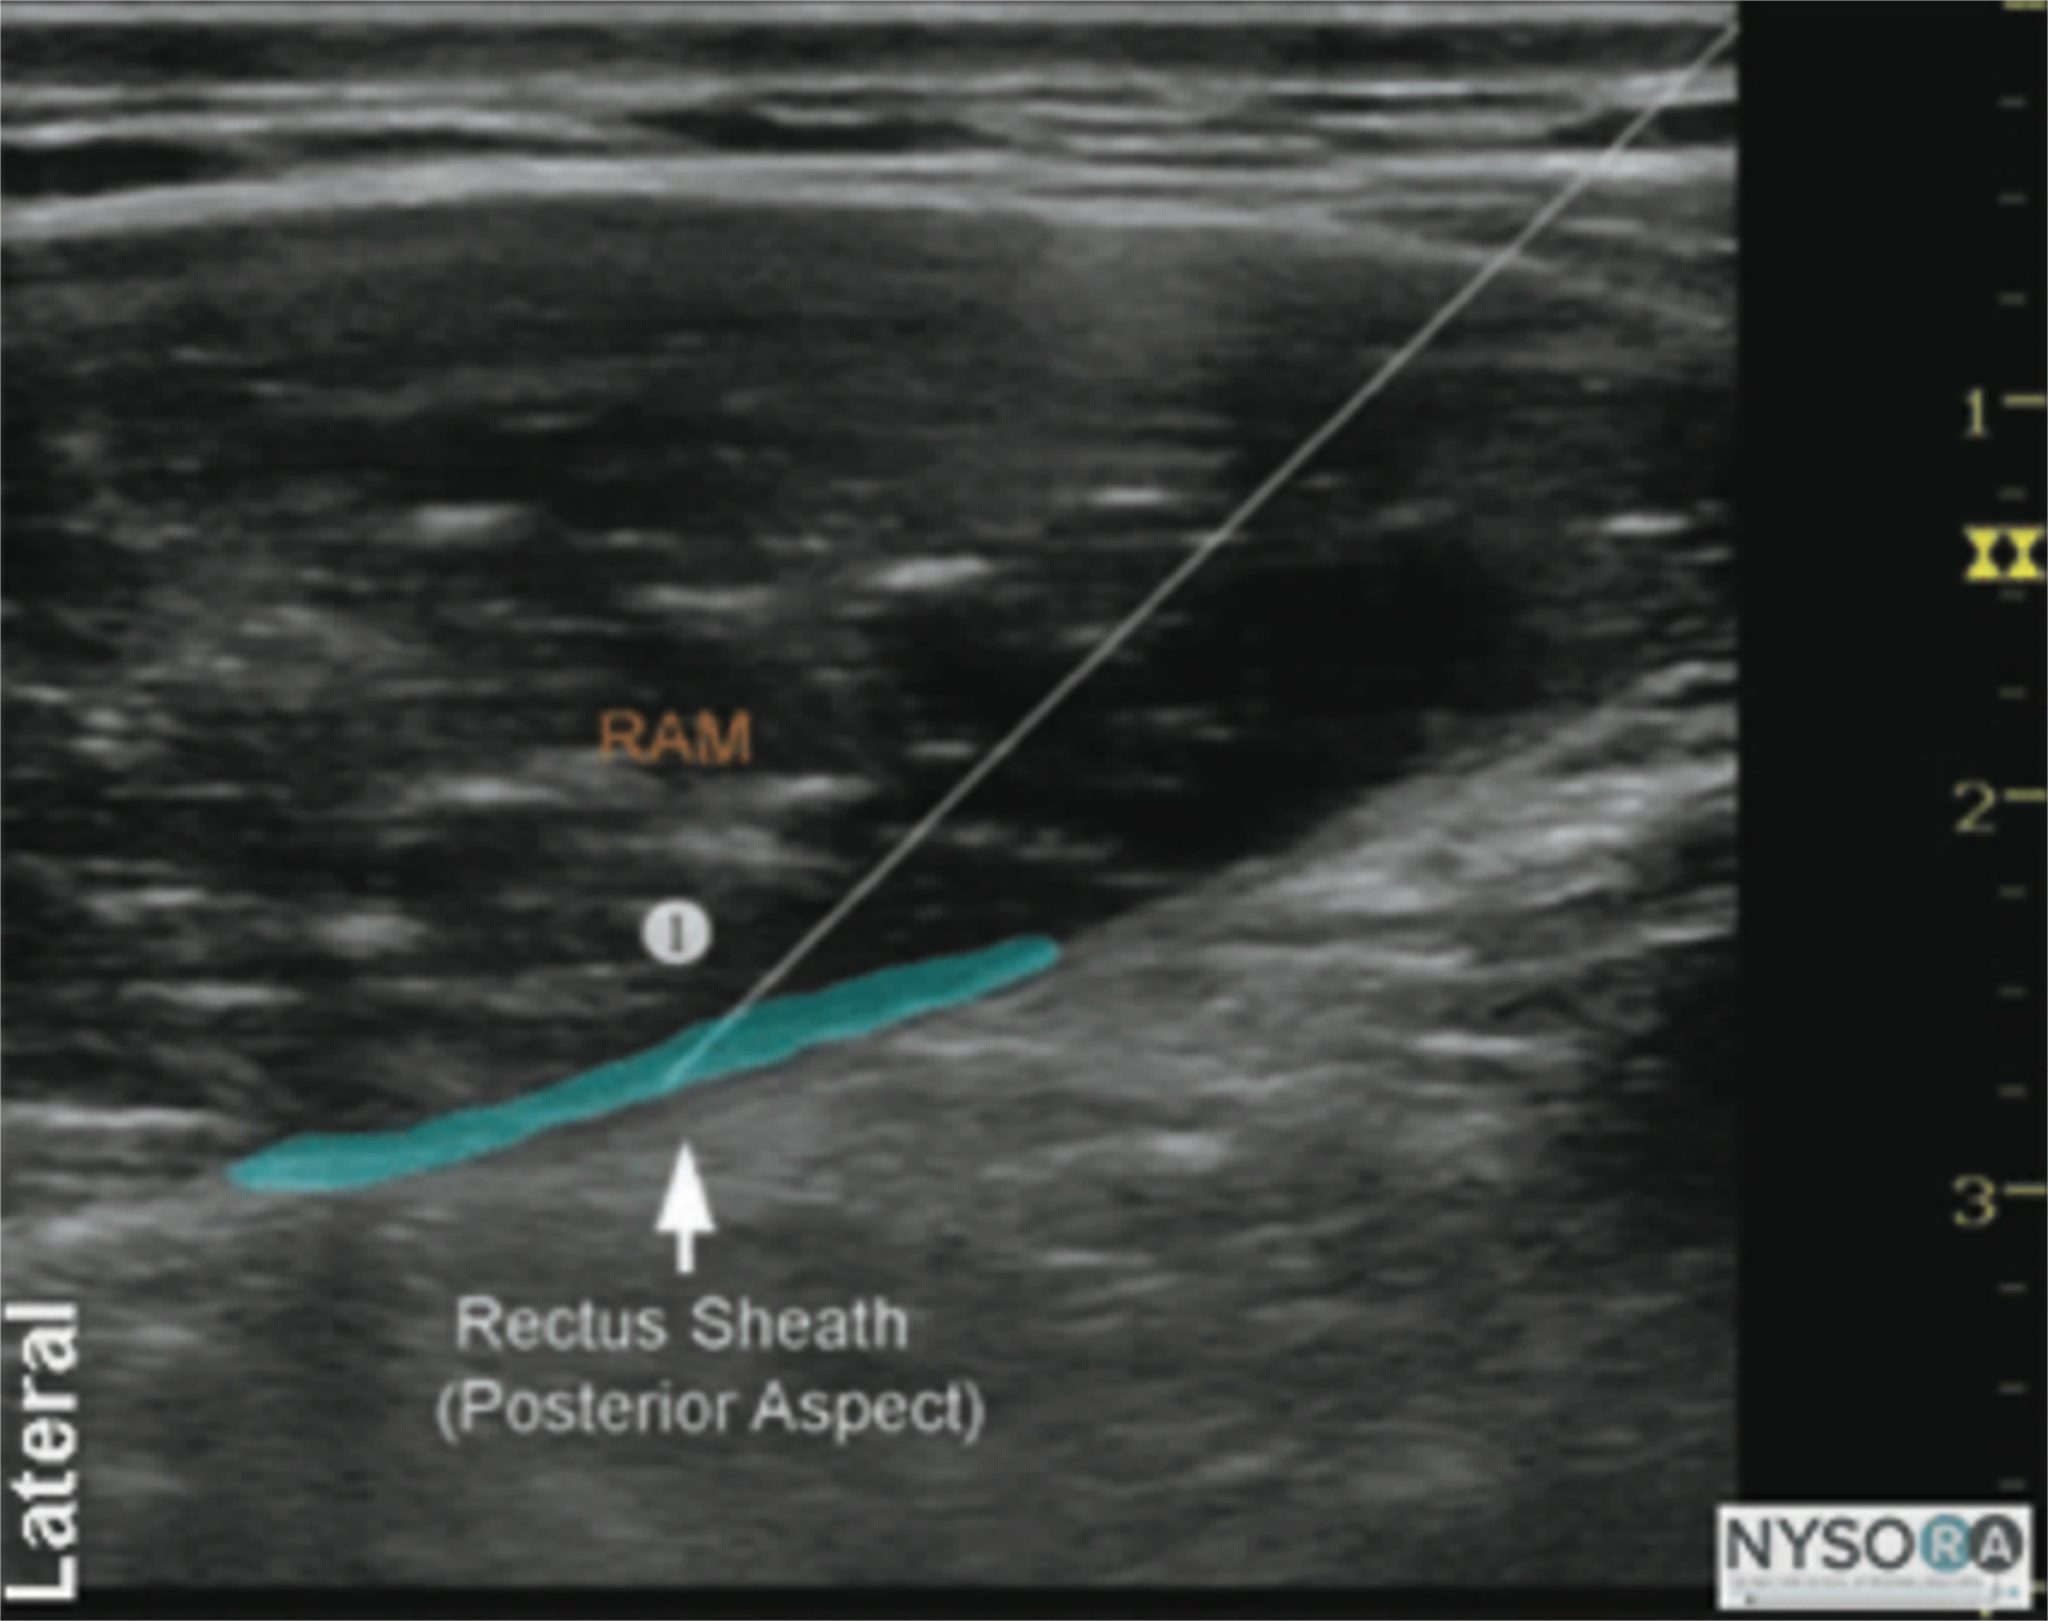

From www.nysora.com

regionalanesthesiaepiduralanesthesiainfographic NYSORA NYSORA Local Anesthesia Stomach Pain Local anesthesia prevents pain during minor medical procedures by numbing a specific part of the body. Local anaesthesia involves numbing an area of the body using a type of medicine called a local anaesthetic. When used on nerve structures (nerve block), specific local anesthetic effects include analgesia (loss of pain sensation) and paralysis (loss of. Local and regional anesthesia numbs. Local Anesthesia Stomach Pain.